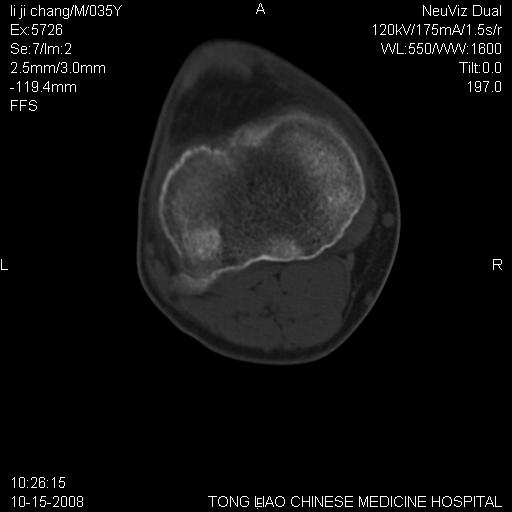

男,35岁,骨科诊断骨性关节炎。继往使用过激素,现股骨头坏死。膝关节病变,请会诊

一元论-----亦考虑为坏死

支持考虑无菌坏死

支持无菌坏死伴退行性骨关节病.

剥脱性骨软骨炎:是一种关节下软骨及软骨下骨缺血性坏死。

支持 无菌性坏死伴退行性骨关节病。

支持无菌坏死伴退行性骨关节病